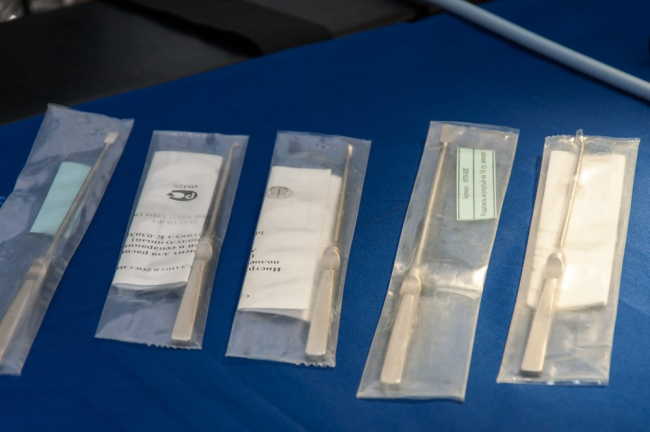

Также с недавнего времени в РКБ функционирует артроскопический комплекс. Его появление в Приднестровье врачи уже назвали прорывом в ортопедии. Современное оборудование позволяет поднять на качественно иной уровень диагностику и некоторые виды операций на суставах.

«Теперь нет необходимости делать большие разрезы, операция осуществляется из двух небольших разрезов, примерно 0,5 см, мы уже провели 10 артроскопий – операций – пациентам с острой травмой, послеоперационный период прошёл гладко», – рассказал врач травматолог-ортопед Александр Гаря.